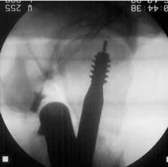

Position des Gerätes in seitlicher Lage ergibt beim Röntgen die folgenden Aufnahmen. Der geriffelte Draht liegt nicht zwischen den zwei glatten Drähten. Bewegen des Zielgerätes ergibt das erforderliche Bild. Sollten die so positionierten Drähte sich nicht über dem Kopf abbilden, muß der Nagel gedreht werden. Auf diese Weise erreicht man die korrekte Lage der Schenkelhalsschraube in die Mitte des Kopfes, ein Auswandern der Schraube ist so unmöglich.